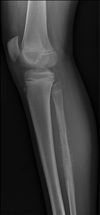

2

3

4